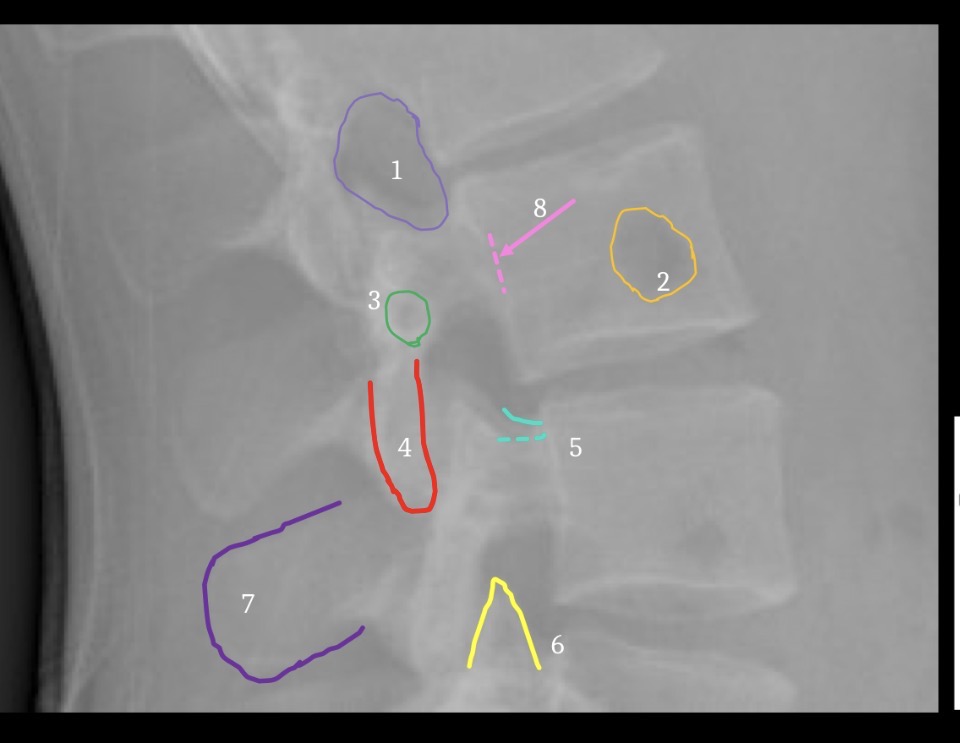

1

T12-L1 intervertebral foramen

2

Rib 12

3

Inferior articular process L2

6

Greater sciatic notch

5

Sacral canal

8

Sacral promontory

9

Iliac crest (2)

11

Transverse process L4

10

Superior articular process L5

12

Anterior body margin of L4

14

Anteriorsuperior body corner L3

15

Intervertebral disc space L1-2